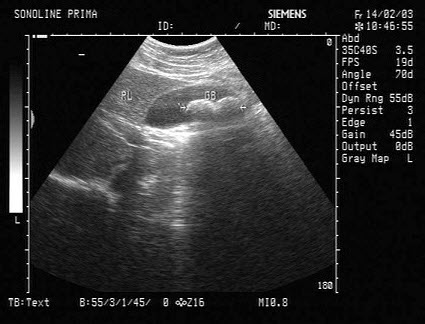

4、单项选择题

某患者脾脏声像图表现如图,诊断为()

A.正常脾脏

B.脾大

C.脾破裂

D.脾梗死

E.以上都不是